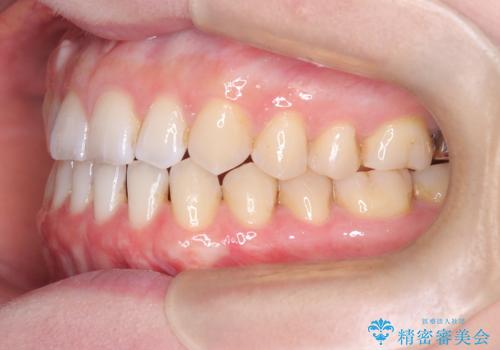

すきっ歯・切端咬合・空隙歯列|インビザラインで11ヵ月で治療完了

- すきっ歯と切端咬合(上下の前歯が先端で当たるかみ合わせ)を主訴にご来院された患者様です。

矯正検査を行った結果、非抜歯でインビザラインによる治療が可能と判断し、マウスピース矯正で改善を行いました。

11ヵ月で矯正治療が終了し、前歯の隙間も改善、見た目とかみ合わせも良好な状態となり、患者様にも大変ご満足いただけました。